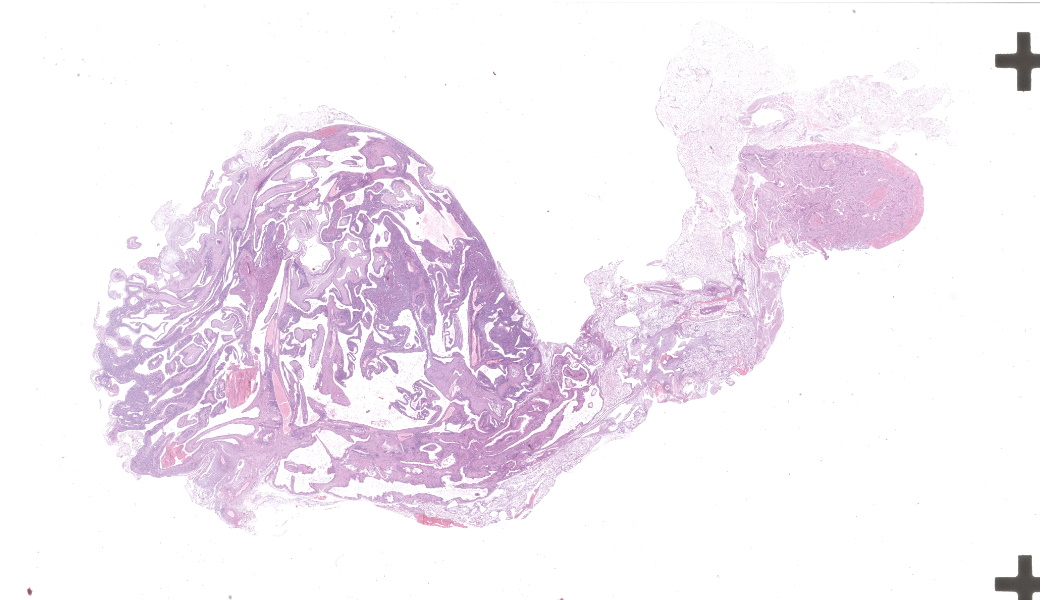

Microscopic Description:

Left kidney: The left kidney is composed of multiple, largely dilated cavities that divide the kidney into numerous islands of parenchyma. These cavities are lined by 2–4 layers of cuboidal to highly columnar, eosinophilic epithelial cells with no mitotic activity (collecting ducts). Few sloughed epithelial cells and erythrocytes are present in the lumen of these ducts. The parenchyma contains islands of immature glomeruli with peripheral nuclei, poorly developed capillaries, and thickened Bowman’s capsule (vimentin positive). Primitive tubules are lined by large basophilic cuboidal epithelial cells with minimal or absent lumina. Other areas within the parenchyma consist of mature tubules and glomeruli with some tubules showing mild dilation and intraluminal protein casts. Collecting duct-like structures are multifocally surrounded by loosely arranged mesenchymal tissue (primitive mesenchyme). The interstitium is multifocally expanded by fibrous connective tissue and some areas are infiltrated by low to intermediate numbers of lymphocytes, plasma cells, macrophages, and occasional neutrophils. Some arteries are very prominent (large) with thickened media, and they appear tortuous. A medium sized artery is surrounded and infiltrated by inflammatory cells predominantely macrophages, neutrophils and occasionally multinucleated giant cells within adventitia, media and intima (transmural). Diffuse proliferation of fibroblasts and deposition of fibrin within the vessel wall is observed. Occasionally, the tunica intima is disrupted. Endothelial cell proliferation is evident with clustering of endothelial cells attempting to recanalize the affected lumina.

Left ureter: Multiple longitudinal and cross-sections of the ureter are present, consisting of urothelium, lamina propria, a smooth muscle layer, and an outer adventitial layer. The periureteral mesenchymal tissue similar to persistent mesenchyme was observed surrounding left ureter and multifocally contains fibrin and exhibits multifocal moderate hemorrhage, and is infiltrated by inflammatory cells, predominantly neutrophils and macrophages, with the presence of hemosiderophages.

- Multicystic renal dysplasia with focal rupture of the capsule.

- Mild to moderate multifocal chronic lymphoplasmacytic tubulointerstitial nephritis.

- Severe diffuse chronic histiocytic arteritis

JPC Diagnoses:

- Kidney: Congenital hydronephrosis, severe, with tubular and glomerular atrophy, interstitial fibrosis, mild lymphoplasmacytic interstitial nephritis.

- Kidney: Asynchronous maturation, with fetal glomeruli, rare primitive tubules, and primitive mesenchyme.

- Kidney, arteries and arterioles: Arteritis, neutrophilic and histiocytic, proliferative and necrotizing, chronic, multifocal, severe.